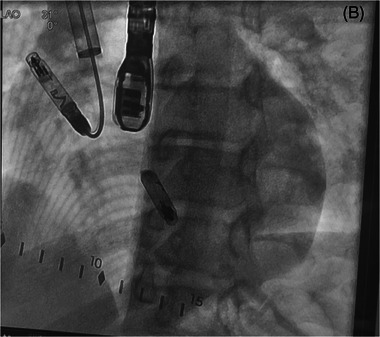

Dual Chamber Aveir Retrievable Leadless Pacemaker Implant via the Right Internal Jugular Vein in a 13-Year-Old With Congenital Complete Heart Block.

Introduction: Congenital complete heart block is a condition where there is a risk of Stokes Adam's attacks and sudden death may occur. Once the escape rate is too low, or other high-risk factors occur, these patients ultimately need pacemakers placed. Epicardial or transvenous pacemakers have typically been in employed dependent on size of the patient and other circumstances. We describe the first case of an implant via internal jugular vein (right) of a dual chamber leadless pacemaker implant in a symptomatic pediatric patient with congenital complete heart block.

Case: A 13-year-old presented with presyncope at rest after years of being followed for her congenital complete heart block. Her average rate on Holter monitoring was below 50 bpm, which coincided with her recent symptoms. After discussion with family, and our own cardiology/surgical team, she had a dual chamber leadless pacemaker implanted. Stable 3-month atrial parameters included an impedance of 340 Ω, sensing of 3.2 mV, and threshold of 0.25 V at 0.2 ms, while ventricular parameters showed an impedance of 780 Ω, sensing of 14.2  mV, and threshold of 0.5 V at 0.2 ms.

Conclusion: Dual chamber leadless pacemaker implant is feasible via right internal jugular vein access and in a pediatric patient.